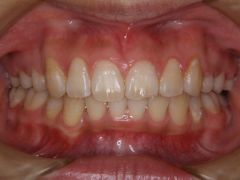

初診時年齢17歳の女子 上下顎前歯の著しい叢生を主訴に来院された。

大臼歯関係は上顎が下顎より前方にあり、叢生に加え上下の歯の咬合関係にも大きなずれがあった。顎外固定装置(ヘッドギア)を併用し上下顎マルチブラケット装置を使用して、上下顎小臼歯を抜歯していただき動的治療を行った。 動的治療期間2年3か月間(調整来院25回)